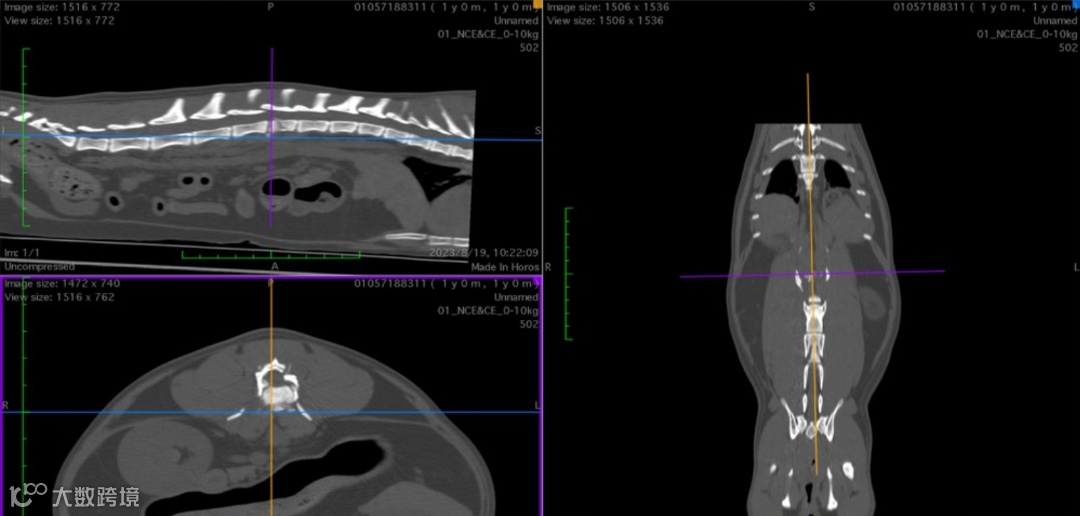

通过对腰椎、腹部的增强扫描发现

L2椎体粉碎性骨折,累及椎体、左侧椎弓根及椎板。

L3右侧横突骨折。